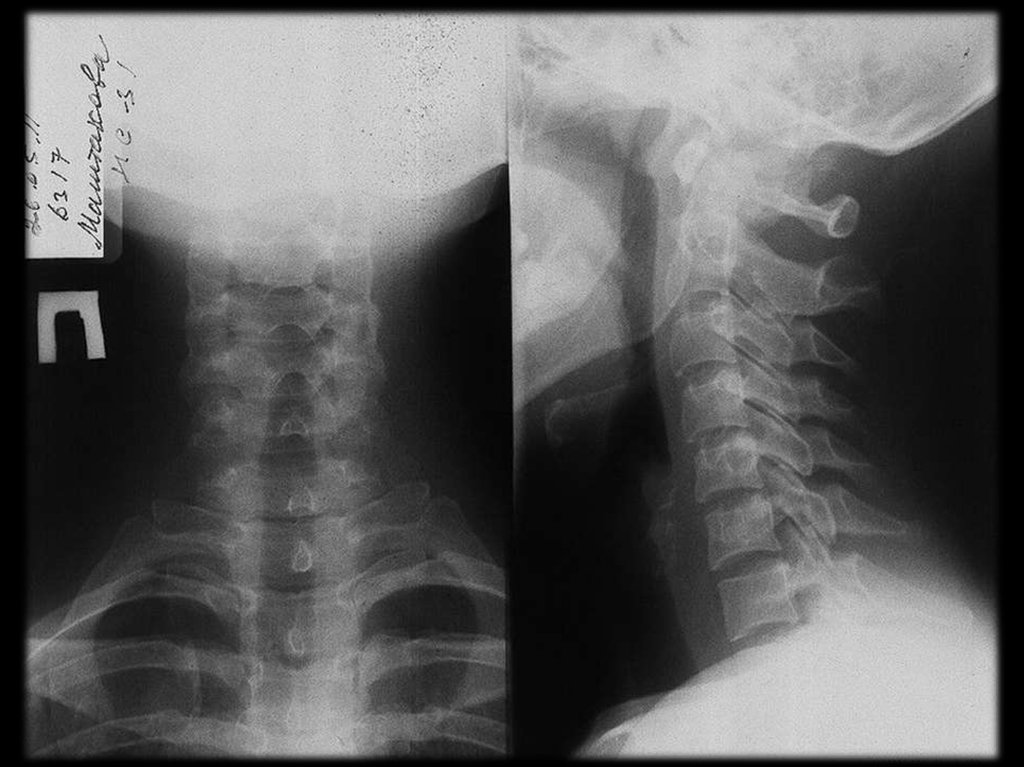

В шейном отделе клинически наиболее значимы

остеофиты

и

артрозы

унковертебральных

сочленений.

остеофиты и артрозы унковертебральных сочленений.